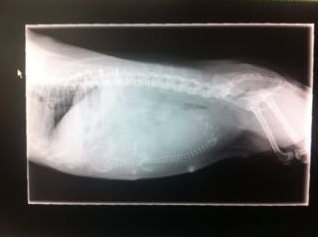

Holle was a 2.5 kg dog that was brought into Sydney Animal Hospitals experiencing trouble giving birth. She was taken in for x-rays and the it turned out that the reason she was having such trouble was that her puppy weighed 110g, far too large for her to deliver naturally.